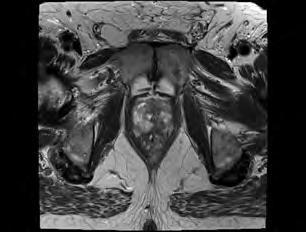

Prostatakrebs sicher erkennen

Multi-parametrische MRT mit hochauflösendem 3-Tesla-Gerät bietet hervorragende Diagnostik

Die derzeit aussagekräftigste und schonendste Tumor-Diagnostik der Prostata bietet die multi-parametrische MRT (Magnetresonanztomographie oder Kernspintomographie) mit einem hochauflösenden 3-Tesla-Gerät . Die multiparametrische Prostata-MRT ist das genaueste bildgebende Diagnoseverfahren zur Frühdiagnose, Ausbreitungsdiagnostik und Verlaufskontrolle des ProstataKarzinoms.

Nach der aktuellen deutschen Leitlinie zur Früherkennung und Therapie des Prostatakarzinoms von 2021 soll – wenn möglich – bei auffälligen PSA-Wert noch vor der Biopsie (Probenentnahme) eine multiparametrische Prostata-MRT durchgeführt werden. Mit dieser Untersuchung können verdächtige Bezirke in der Prostata erkannt werden. Aufgrund seiner hervorragenden Genauigkeit in der Darstellung kann damit einem Teil der Patienten möglicherweise eine Biopsie sogar erspart werden. Aus den in der MRT erkannten, „verdächtigen“ Areale können dann in einem zweiten Schritt gezielt Gewebeproben im Rahmen der Biopsie entnommen werden.

Die radiologische Untersuchung umfasst eine hochauflösende, morphologische MRT der Prostata in mehreren Ebenen, eine Perfusionsbildgebung (Durchblutungsmessung) mit KontrastmittelInjektion, sowie eine Diffusionsbildgebung (DWI) zur Beurteilung der Molekularbewegung des Gewebes. Erst die Kombination dieser MRT-Techniken an einem hochauflösenden 3-Tesla-MRT ermöglicht es, den Krebs in der naturgemäß „unübersichtlichen“ Prostata (vergrößert, knotig, verkalkt) zu entdecken. Die Bildanalyse erfolgt in Form einer

strukturierten Befundauswertung nach dem aktuellen PIRADs–Standard, der die Kommunikation zwischen Ärzten erheblich verbessert.

Ein Prostatakrebs wird mit Hilfe dieser minimal-invasiven Behandlungsmethode in etwa 80 Prozent der Fälle eindeutig erkannt und in seiner Struktur sowie Beschaffenheit optimal dargestellt. Die Untersuchung ist für den Patienten besonders schonend, da keine Spule in den Enddarm eingeführt werden muss. Da außerdem bei der MRT keine Strahlen angewendet werden, eignet sich die Untersuchung problemlos für eventuelle Verlaufskontrollen. Auch nach einer MRT ist für die endgültige Diagnosestellung „Prostata-Krebs“ eine Biopsie erforderlich. Mit Hilfe der MRT kann die Biopsie jedoch gezielt vorgenommen werden. kann somit eine wichtige Rolle bei der Diagnosestellung des Prostata-Karzinoms übernehmen und wegweisende Informationen für die weitere, optimale Behandlung

Morphologisches T2-Bild (oben) und Diffusionsbild (DWI, unten) mit tumorverdächtigen Arealen (rot) links in der hinteren peripheren und vorderen Transitionalzone der Prostata.